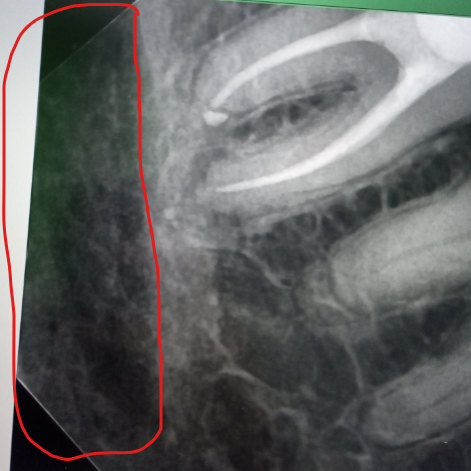

alewka213213 Опубликовано 11 декабря, 2024 Автор Поделиться Опубликовано 11 декабря, 2024 (изменено) 7 часов назад, Carioznik сказал: Не знаю, нужно разбираться и не по интернету , а произвести нормальный осмотр, собрать анамнез, посмотреть все рентгенологические исследования, возможно, сделать ещё дополнительные и тогда уже что-то, более- менее, можно будет сказать. Извиняюсь за еще один вопрос, а это что за область (отметил красным)? Если до этой области дойдет воспаление, будет худо? Просто подозреваю, что это костная ткань челюсти или нерв какой-то. А может просто снимок такой) Изменено 11 декабря, 2024 пользователем alewka213213 Ссылка на комментарий

АнтонТЛТ Опубликовано 11 декабря, 2024 Поделиться Опубликовано 11 декабря, 2024 Это нижнечелюстной канал, в нем проходят нерв и сосуды. Как правило не затрагивается даже при очень сильных воспалениях. Ссылка на комментарий

alewka213213 Опубликовано 11 декабря, 2024 Автор Поделиться Опубликовано 11 декабря, 2024 1 час назад, АнтонТЛТ сказал: Это нижнечелюстной канал, в нем проходят нерв и сосуды. Как правило не затрагивается даже при очень сильных воспалениях. А если выделенная мной область - область воспаления, то шансы высоки, что воспаление затронет нижнечелюстной канал? Выглядит так, будто очень близко воспаление Ссылка на комментарий

АнтонТЛТ Опубликовано 11 декабря, 2024 Поделиться Опубликовано 11 декабря, 2024 Не высоки, воспаление пойдет по пути наименьшего сопротивления (там где кость мягче) Ссылка на комментарий